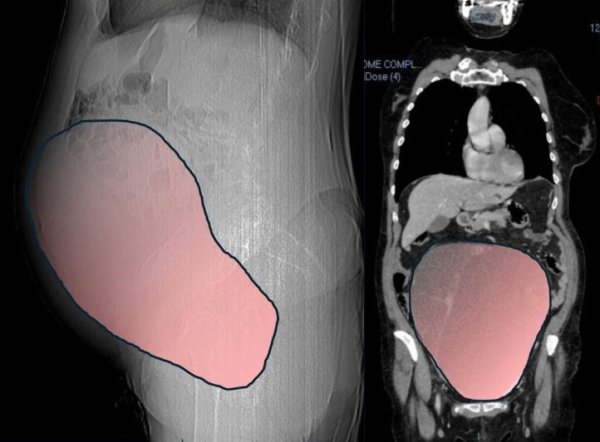

यह मामला इटली के ट्यूरिन शहर का है। जानकारी के अनुसार, 69 वर्षीय महिला को कई महीनों तक इस बात का अंदाजा ही नहीं था कि उसके पेट में एक विशाल ट्यूमर तेजी से विकसित हो रहा है। समय के साथ यह ट्यूमर इतना बड़ा हो गया कि इसका आकार लगभग एक पूर्ण अवधि के नवजात शिशु जितना हो गया। हालात तब और गंभीर हो गए जब यह डिम्बग्रंथि (ओवेरियन) ट्यूमर महिला की बड़ी आंत (कोलन) पर दबाव डालने लगा।

करीब छह घंटे तक चली इस बेहद जटिल और चुनौतीपूर्ण ऑपरेशन में सर्जन टीम ने 28 सेंटीमीटर लंबे ट्यूमर को सफलतापूर्वक शरीर से बाहर निकाल दिया। जब ट्यूमर को तौला गया तो उसका वजन करीब 6 किलोग्राम (लगभग 13 पाउंड) निकला, जिसे देखकर डॉक्टर भी हैरान रह गए। ट्यूरिन के ‘सिटी ऑफ हेल्थ एंड साइंस’ अस्पताल ने इसकी तुलना “पूर्ण अवधि की जुड़वां गर्भावस्था” से की है। अस्पताल के अनुसार, महिला में सबसे गंभीर लक्षण आंतों से जुड़ी समस्याओं के थे, जिनसे निपटने के लिए कई विशेषज्ञों को तुरंत और मिलकर इलाज करना पड़ा।